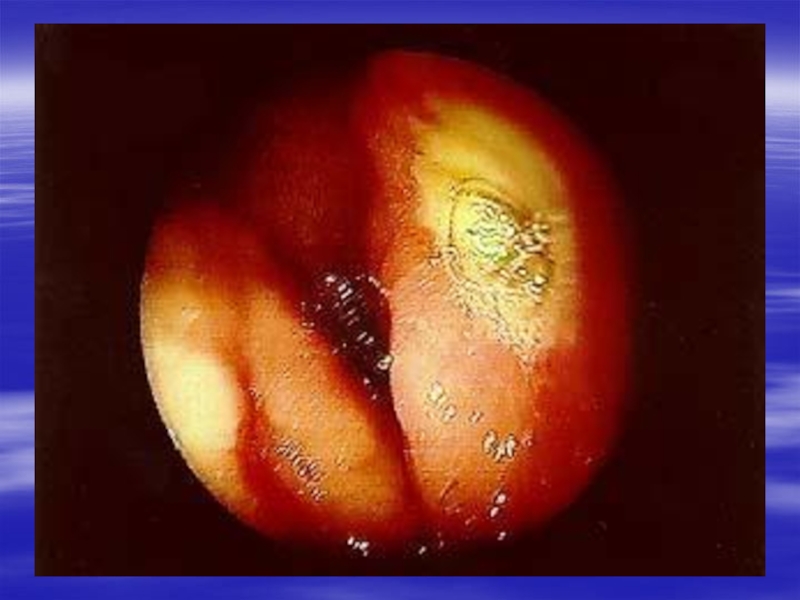

Слайд 7ПАТОМОРФОЛОГИЯ

Основной морфологический субстрат ЯБ - язвенный дефект слизистой оболочки, а

также сопряженный с ним гастродуоденит.

Морфологически различают острую и хроническую

язву.

Острая язва характеризуется некрозом и деструкцией, захватывающей не только эпителий слизистой оболочки, но и распространяющейся на подслизистый и мышечный слои. В этом главное отличие язвы от эрозии, которая характеризуется только дефектом эпителия.

Заживление язвы происходит путем рубцевания (поврежденный мышечный слой не регенерирует, а замещается соединительной тканью), эрозия же эпителизируется без рубцевания.

Для хронической язвы типичны атрофия слизистой оболочки (желез), разрастание соединительной ткани, метаплазия эпителия.